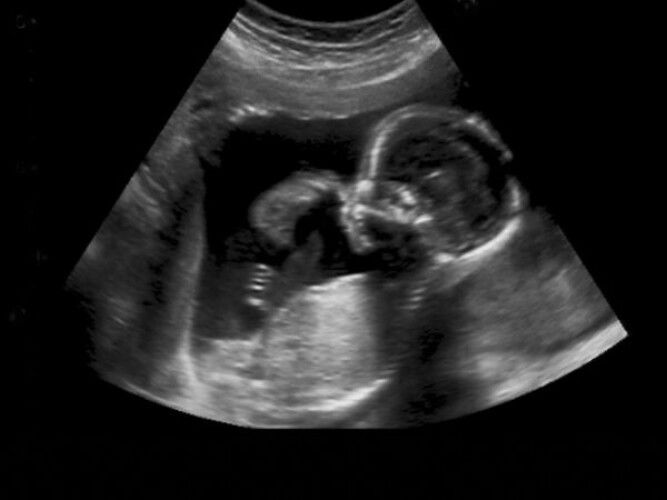

How did you feel when you saw your baby on the first scan?